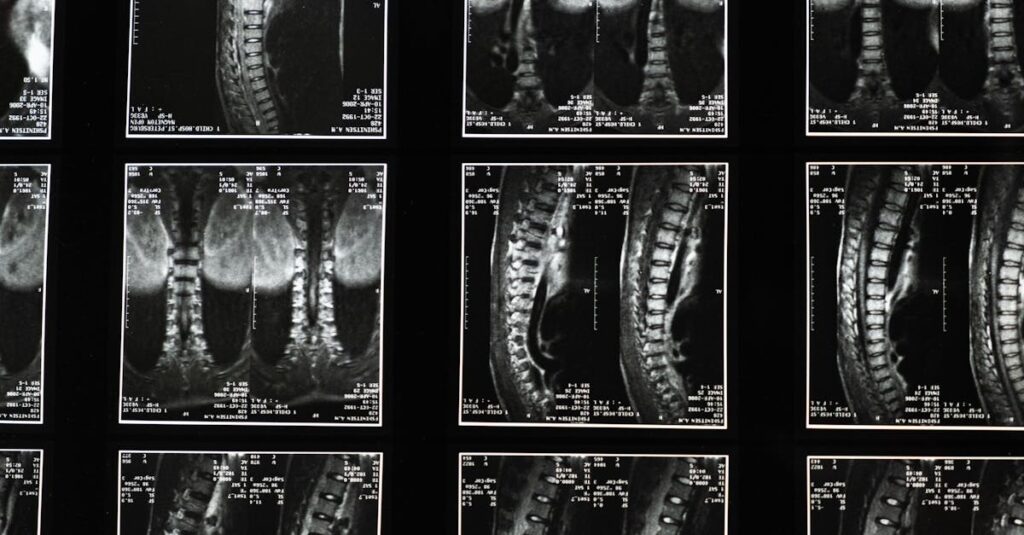

Quels examens permettent de diagnostiquer une hernie discale?

Une IRM ou une radiographie est utilisée pour confirmer le diagnostic d’une hernie discale.

Quels examens sont nécessaires avant de commencer un traitement de décompression?

Une IRM ou une radiographie est généralement nécessaire pour évaluer l’état de la colonne vertébrale.